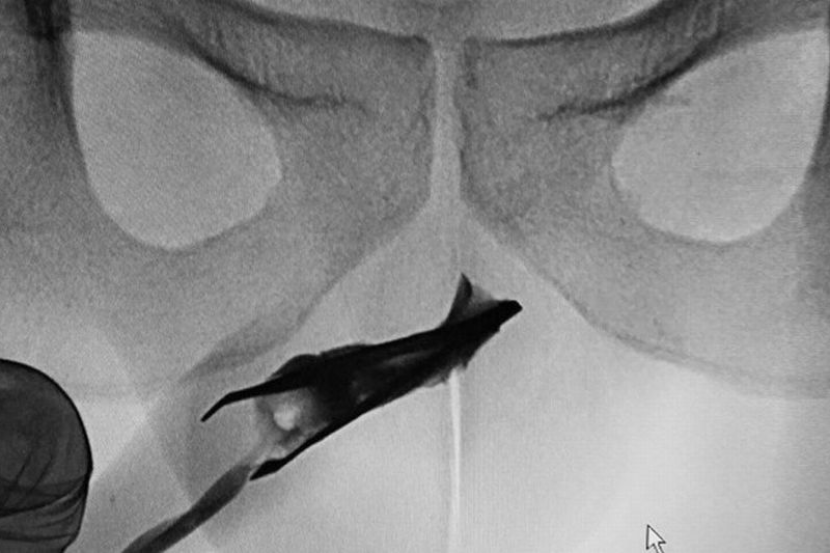

Imbasan x-ray mendedahkan di mana letaknya pengepit itu, yang menunjukkan bahagian hujungnya dalam keadaan mengepit tertanam dalam bahagian atas urethra.

Doktor menggunakan teknik tekanan pada kedua-dua belah zakarnya untuk memastikan alatan berukuran 2.7 inci itu mengepit, dalam usaha mengeluarkannya.

Jika mereka mengeluarkannya semasa ia dalam keadaan biasa (terbuka), bahagian hujungnya yang tajam boleh merosakkan saluran tersebut.